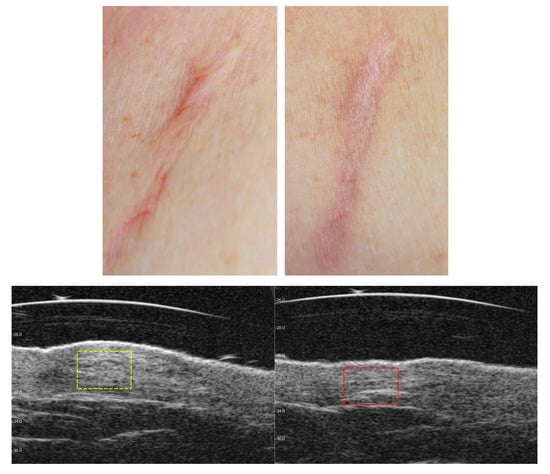

3.3. Visible and Ultrasound Changes in Scar Area